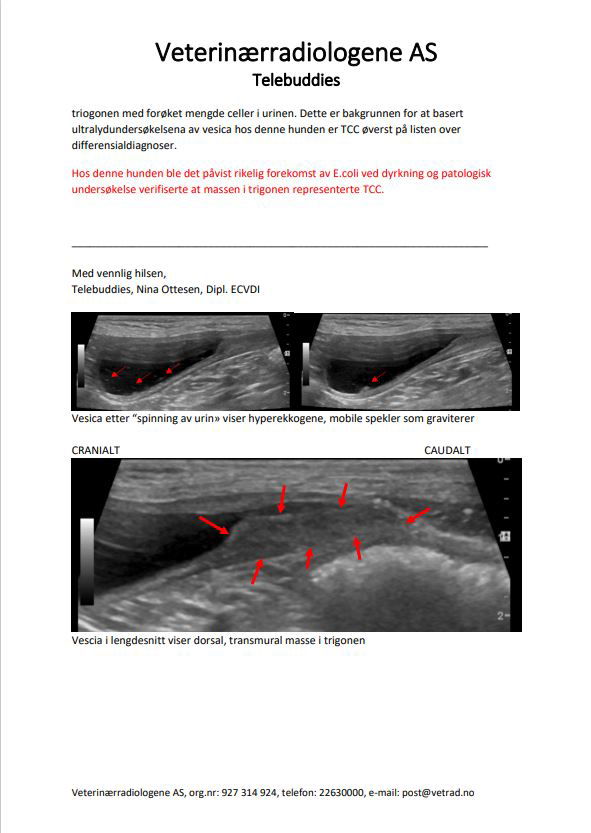

Signalement: Jack Russell terrier, tispe, 13 år Anamnese: Intermitterende hematuri. Tisser inne – selv rett etter lufting